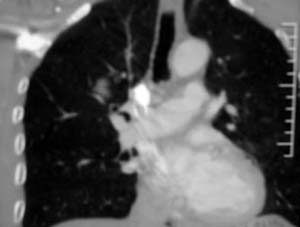

患者,男,58岁,煤矿职工,无症状,单位体检发现病变。

肺窗显示结节的后外边缘呈分叶状生长系生长过程受血管阻挡所致,出现较典型的“树凹”征,部分边缘见毛糙,不均匀强化,楼主未提供增强前后ct值,不好比较,倾向周围型ca。

右肺门上缘见类圆形节结影,密度尚均,边缘清楚,其内可见点状钙化影,周围支气管受压移位,病灶未见明显强化。考虑:1炎性假瘤  2 支持周围型肺ca (腺瘤)

右肺门上缘见类圆形节结影,密度尚均,边缘清楚,其内可见点状钙化影,周围支气管受压移位,病灶未见明显强化。考虑:良性病变——结核球可能性大,周围型肺癌待排。

病灶边缘光滑,似可见分叶征,未见明显毛刺。气管影轻度向右偏移。内可见点样钙化。邻近气道影通畅,考虑结核球可能。请楼主尽快公布结果

病灶呈分叶型,边缘清晰,无毛刺,增强强化不明显,内见多发钙化,亦无卫星灶。多考虑良性病变。错构瘤可能性大。

病灶呈分叶型,边缘清晰,无毛刺,增强强化不明显,内见多发钙化,亦无卫星灶。多考虑良性病变。错构瘤可能性大或结核球。肺癌待排

动脉相上,右上肺动脉的尖段分支位于结节旁,结节对血管形成压迫而使到走行略改变,并没有很明确的包绕,也没有动脉期的供血,考虑还是偏向于良性可能大。当然最后的决定还是病检

病变边界清晰,对周围主要是外压性改变,未见血管包绕,边缘及中心见钙化,考虑良性病变,结核球可能